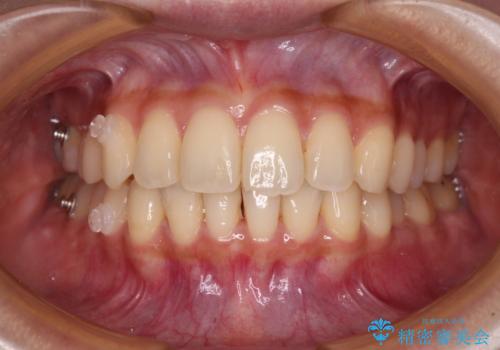

- 前歯のデコボコと強い咬みしめを気にして来院された患者様です。

インビザラインを用いて、前歯の叢生を解消するとともに、ディープバイトを改善していくこととしました。

海外へ転居する予定があったため、1日22時間以上の装着時間をしっかりと守っていただき、予定期間よりも早く、思っていた以上にきれいに仕上げることができました。